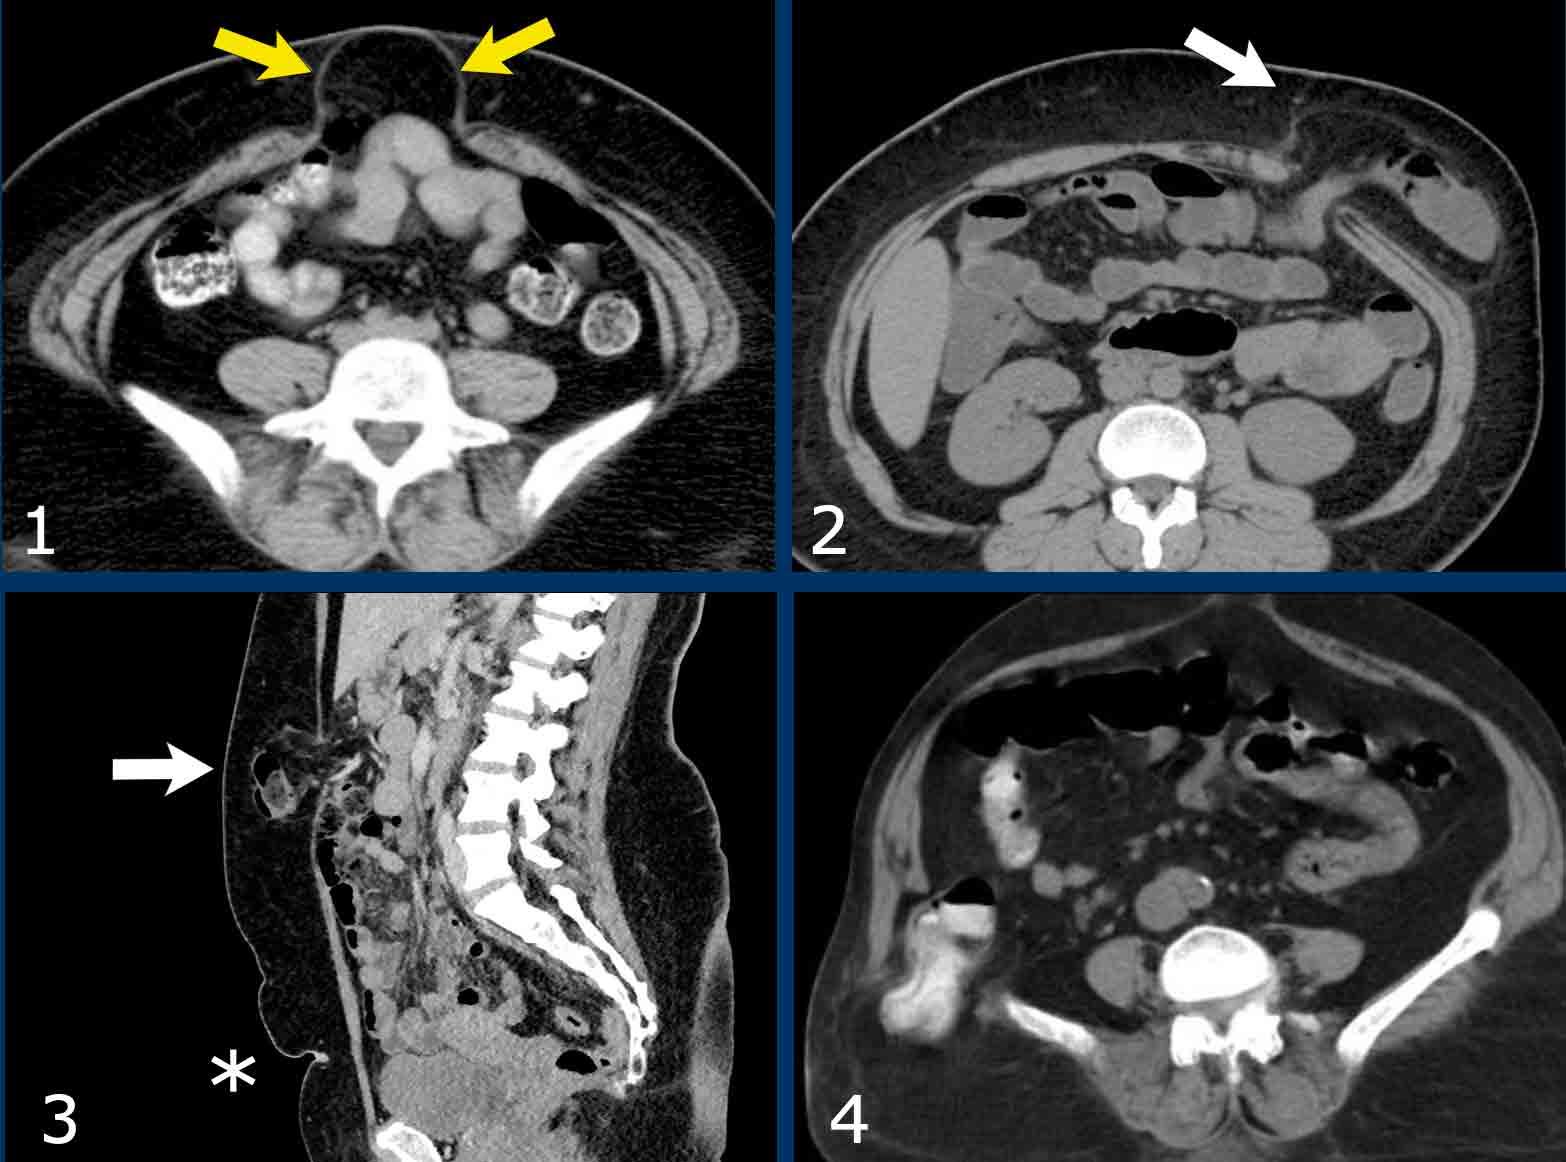

Đo kích thước trong trường hợp nhiều thoát vị

Bệnh nhân này có hai thoát vị.

Có một thoát vị đường giữa (đầu mũi tên màu vàng) và một thoát vị bên (đầu mũi tên màu trắng).

Trong trường hợp này, tổng chiều dài kết hợp và tổng chiều rộng được đo.